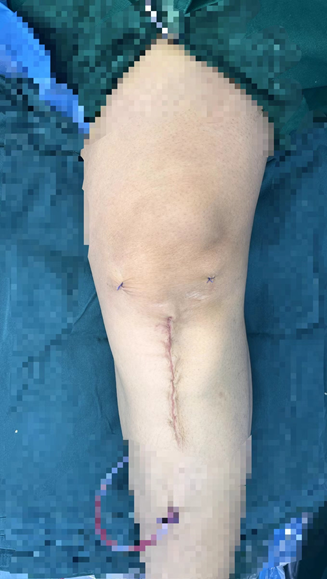

手术中,关节组医师团队凭借精湛技艺,犹如一位“骨骼工程师”,精确地调整了患者的下肢力线,将压力从磨损的内侧成功转移至健康的外侧。术后患者膝关节疼痛症状迅速缓解,并于次日开启康复训练,重燃运动希望。